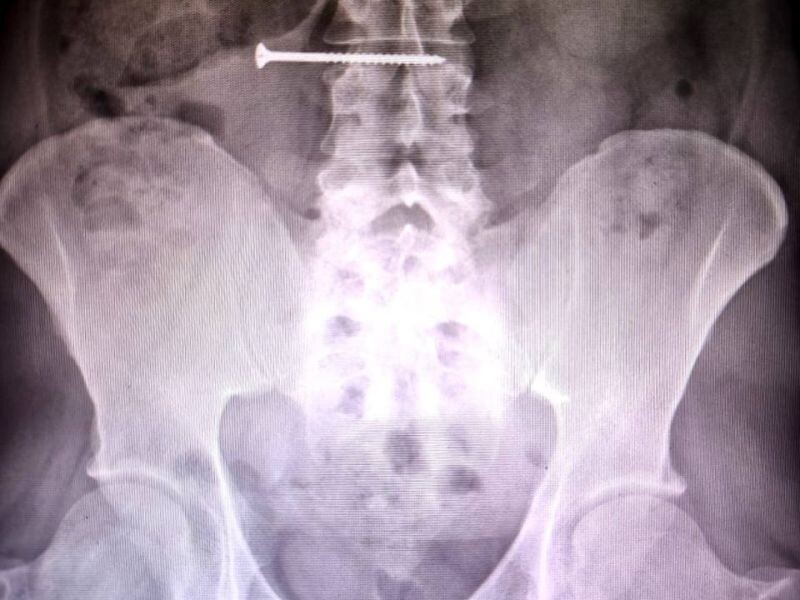

Красноярские врачи спасли случайно проглотившего саморез мужчину Мужчина обшивал свой дом сайдингом и случайно проглотил саморез. Пациент был экстренно прооперирован: хирурги совместно с врачами-эндоскопистами успешно извлекли саморез длиной 50 мм. Контрольное эндоскопическое исследование показало, что повреждений стенок желудка и кишечника нет. В настоящее время пациент проходит лечение в отделении хирургии под чутким наблюдением медицинского персонала. Фото: Краевая клиническая больница

Мужчина обшивал свой дом сайдингом и случайно проглотил саморез.

Пациент был экстренно прооперирован: хирурги совместно с врачами-эндоскопистами успешно извлекли саморез длиной 50 мм. Контрольное эндоскопическое исследование показало, что повреждений стенок желудка и кишечника нет.

В настоящее время пациент проходит лечение в отделении хирургии под чутким наблюдением медицинского персонала.

Фото: Краевая клиническая больница